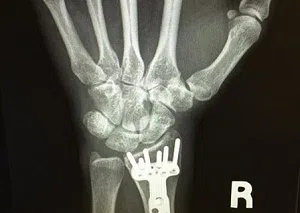

Carrie Underwood Shares Wrist X-Ray

Carrie Underwood took to her Instagram page to share a picture of her most recent visit to her doctor. This included an x-ray of her wrist which she broke in what she called a “freak accident...